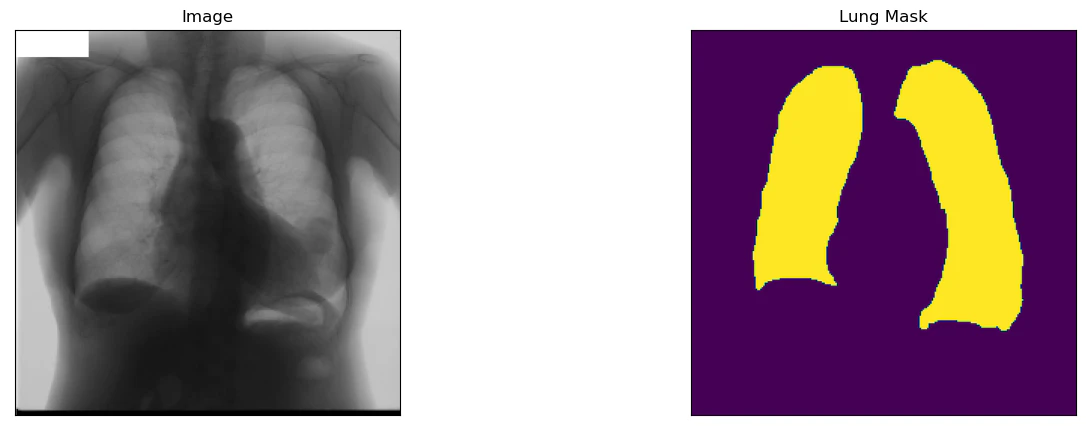

ここではその中のsegmentation02,胸部X線画像の肺野領域抽出データを用いてみます.

このデータは,肺のX線画像に対して肺野領域:255,心臓:85,肺野外:170,体外:0とした255画素値によってラベル化されており,学習用のデータ199枚と評価用の画像48枚で構成されています.

解析対象のラベルを肺(lung)に指定すると以下のような画像が確認できます.